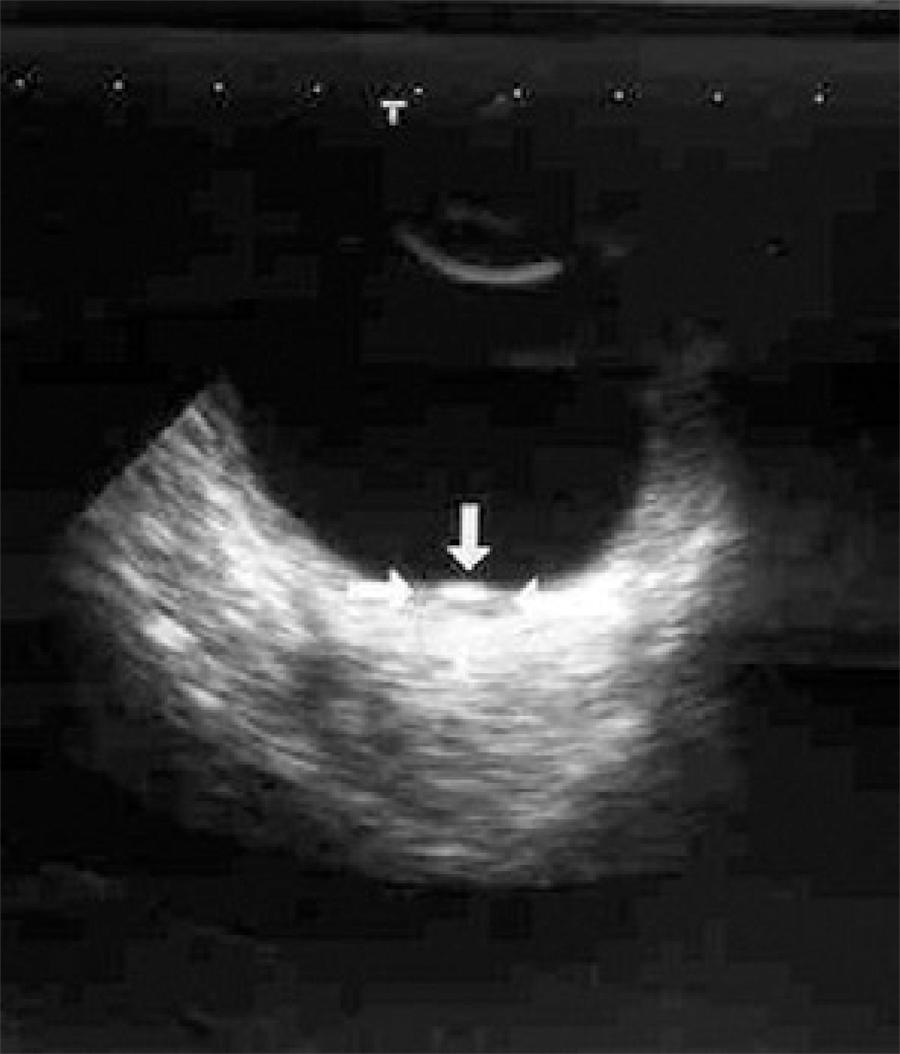

A 49-year-old woman with metastases of pancreatic cancer to liver, spleen, multiple abdominal lymph nodes, and additionally with peritonitis carcinomatosa was presented to the Ophthalmology Department of the Akdeniz University Hospital with a two week history of blurred vision in her left eye two months after the diagnosis. Her best-corrected visual acuities were 20/20 for the right and 20/200 for the left eye. Intraocular pressure and external appearance were normal in both eyes. A slit-lamp examination showed no sign of intraocular inflammation. Fundus examination revealed a white-yellow dome-shaped subretinal mass of 2 optic disc diameters infero-temporal to the macula with minimal subretinal fluid on the right and a white-yellow dome-shaped subretinal mass of approximately 3 optic discs in diameters supero-temporal to the macula with shallow subretinal fluid involving juxtafoveal region (Figure 1). Pigmentary alterations at the border of both lesions were evident. Ocular USG confirmed bilateral choroidal mass, suggestive of metastasis (Figure 2). Although the lesion threatened the vision and demanded radioactive plaque brachytherapy, the medical condition of the patient deteriorated rapidly. Despite further chemotherapy, the patient died six months after the diagnosis of ocular metastasis. During the follow-up bedside exams, a subjective improvement in vision was noted and the left choroidal lesion shrunk to the diameter of one disc with no subretinal fluid. The choroidal dome-shaped mass on the right eye fully regressed and we observed retinal pigmentary changes, two discs in diameter, in place of the original lesion.